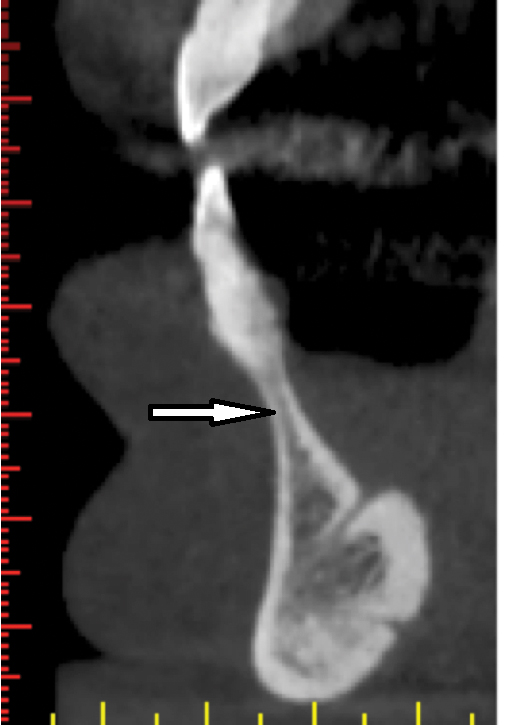

Proceeding anteriorly, the inferior alveolar nerve (IAN) (Figure 2) may descend gently or steeply in the mandible.8 The canal is usually around 3.2-mm wide and surrounded by cortical bone, which does not reliably provide resistance to a twist drill.9 In order to determine the length of a dental implant at a specific site in the posterior mandible, it is advisable to measure from the crest of the alveolar bone to the coronal aspect of the IAN and subtract 2 mm to provide a safety zone.10

Fig 2. Inferior alveolar nerve: panoramic view. The third branch of the trigeminal nerve (mandibular branch) usually descends gently within the mandible (arrow). Other times, it may descend steeply within the mandible.

Figure 2